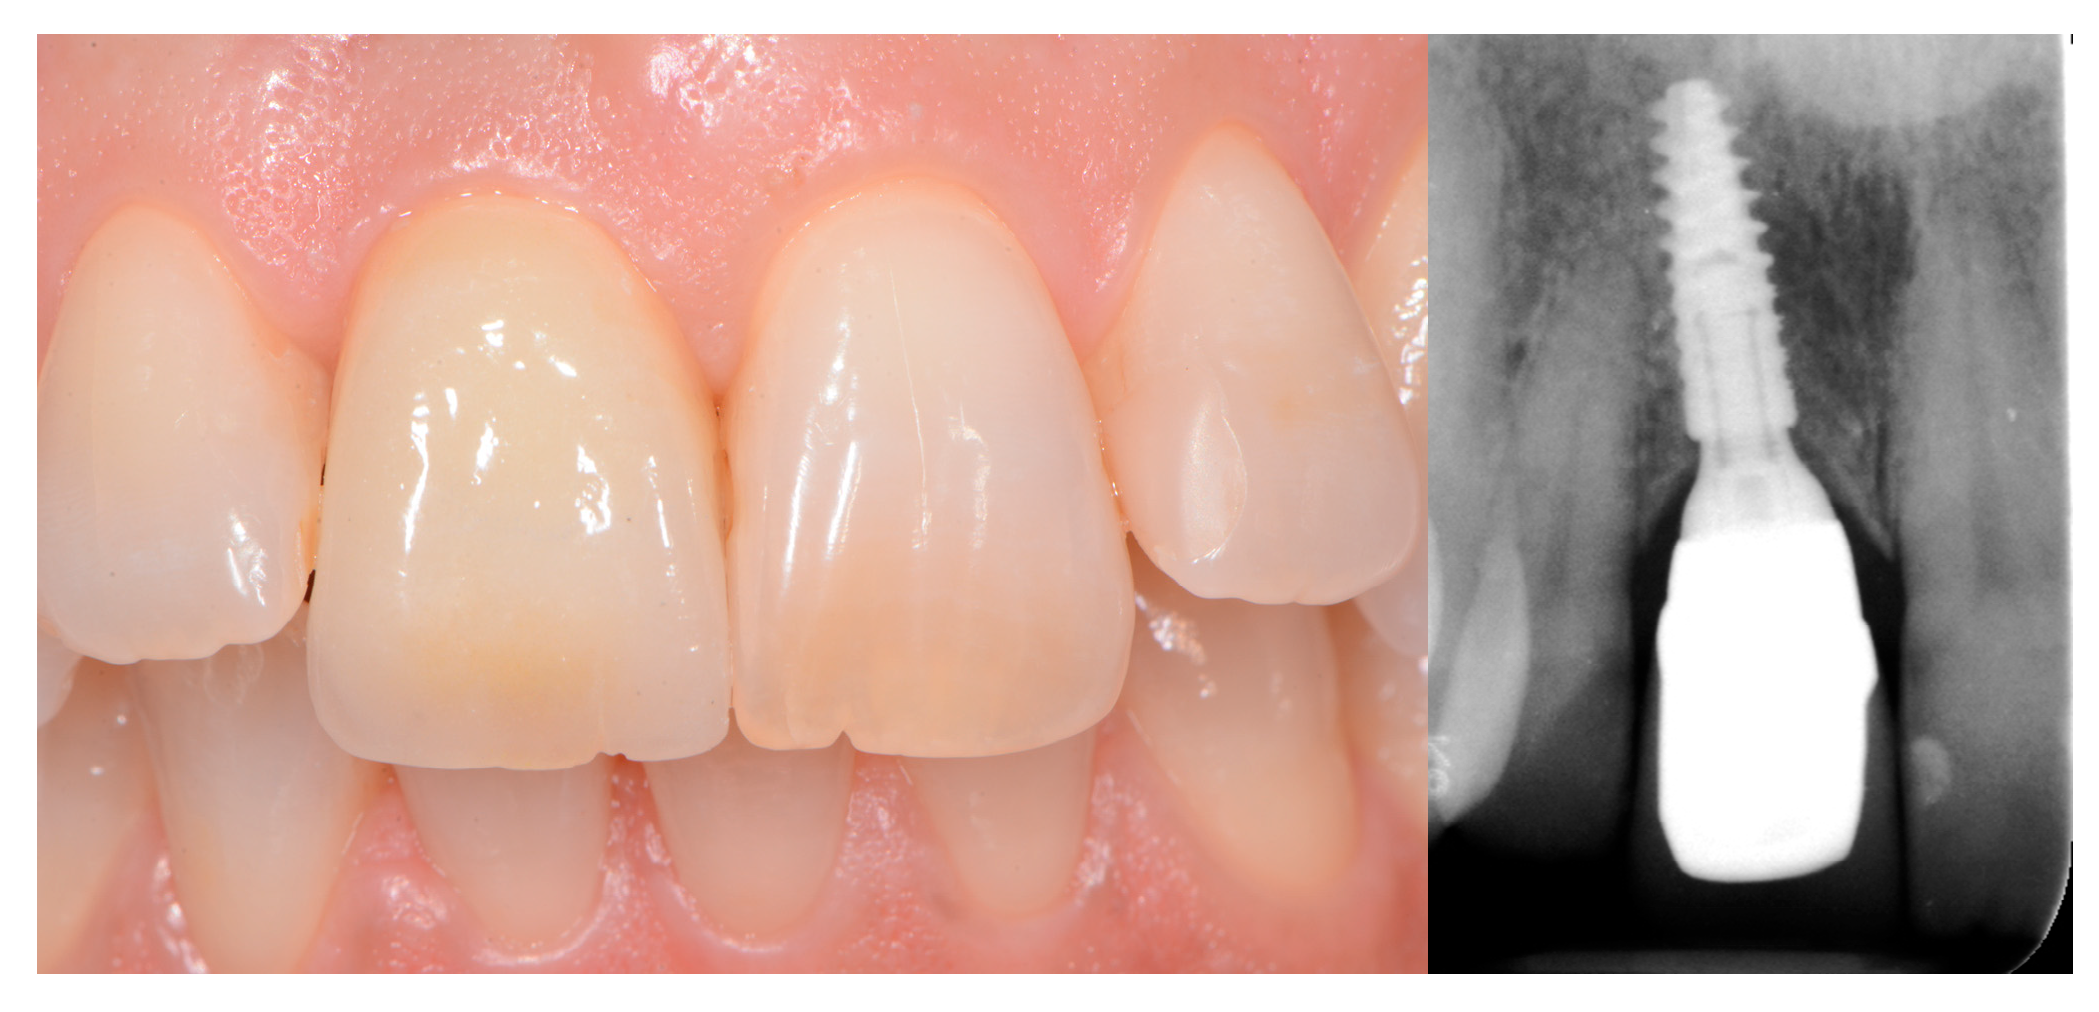

3.1. Single Crowns